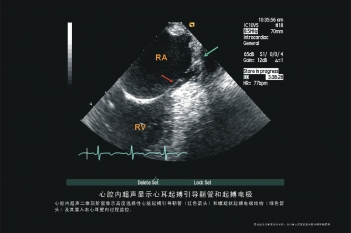

心耳起搏

希氏束起搏电极置放